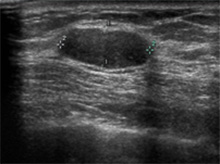

2-3mm 크기의 아주 작은 종괴도 찾아낼 정도로 효율적이나 검사 시간이 많이 소요되고 시술자에 따라 결과 판독의 정확성에 많은 차이가 있으므로 경험 많은 유방 전문 의사에 의해서 시행되어야만 정확한 진단을 내릴 수 있습니다.